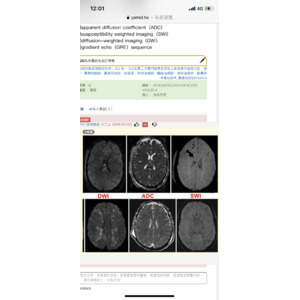

MRI序列